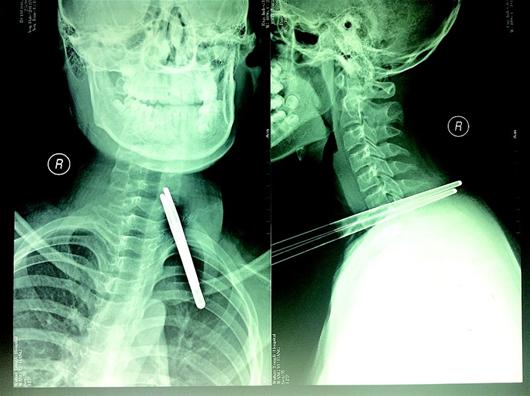

子弹贯穿伤

子弹从前面射进去,从后面钻出去了